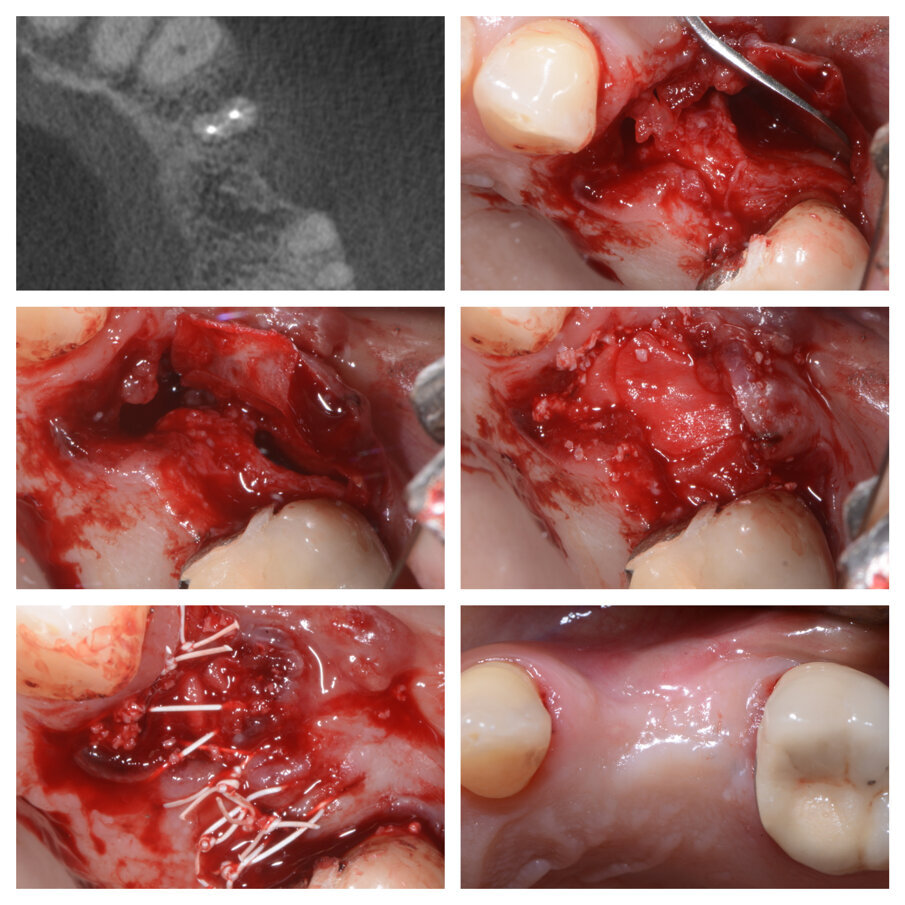

Fig. 1a_Estrazione di radice distale di 46 e innesto su deficit di 45 e 46.

Fig. 1b_Cambiamento dei tessuti a 22 giorni.

Fig. 1c_Aumento orizzontale dei tessuti duri del 50%.

Fig. 1d_Tessuti duri prima e dopo la tecnica S.A.T., posizionamento implantare.

Fig. 1e_Condizionamento tessuti molli e protesi definitiva.